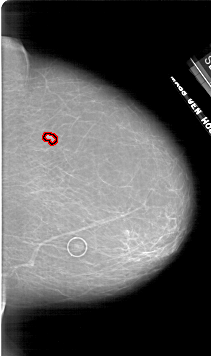

FILE: A_1798_1.RIGHT_CC.OVERLAY

TOTAL_ABNORMALITIES 1

ABNORMALITY 1

LESION_TYPE MASS SHAPE LOBULATED MARGINS ILL_DEFINED

ASSESSMENT 4

SUBTLETY 4

PATHOLOGY BENIGN

TOTAL_OUTLINES 1

BOUNDARY